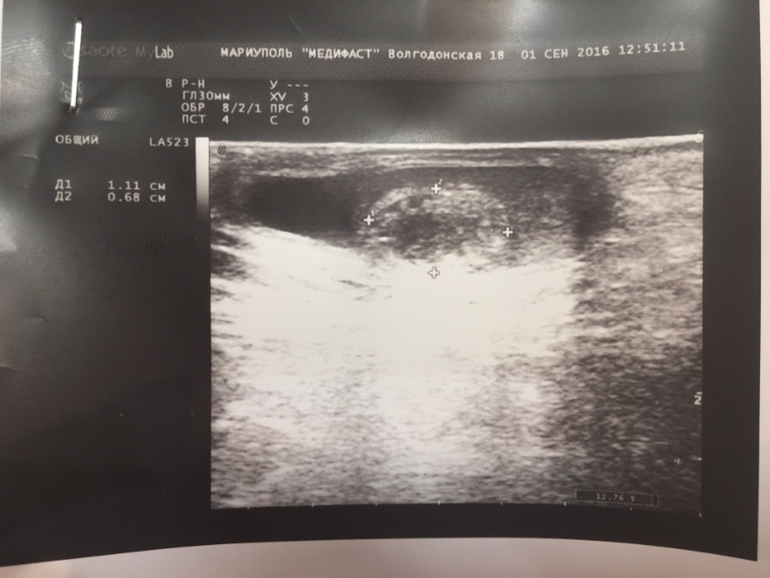

У мальчика 7.5 лет в правом яичке по Узи нашли образование

Здравствуйте,уважаемый доктор!Помогите консультацией!У мальчика сделали узи мошонки по вопросу водянки,обнаружили образование,врачи диагноз установить не могут ,я уже извелась к какому врачу нам бежать и куда ехать с нашей проблемой...сдали дополнительно анализы онкомаркеров и общий анализ .Подскажите что это может быть и в каком направлении двигаться?Буду Вам очень благодарна!

Здравствуйте. По хорошему, надо вас вести очно, все дети с такой патологией наблюдаются у нас с периодичностью 6 мес. Характер образования я могу уточнить только самостоятельно выполнив УЗДГ